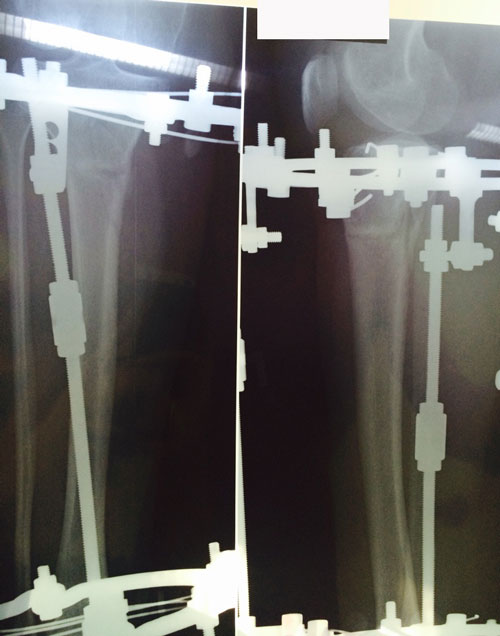

Диагноз: ахондроплазия, варусная деформация обеих голеней 155 градусов.

Исходник.